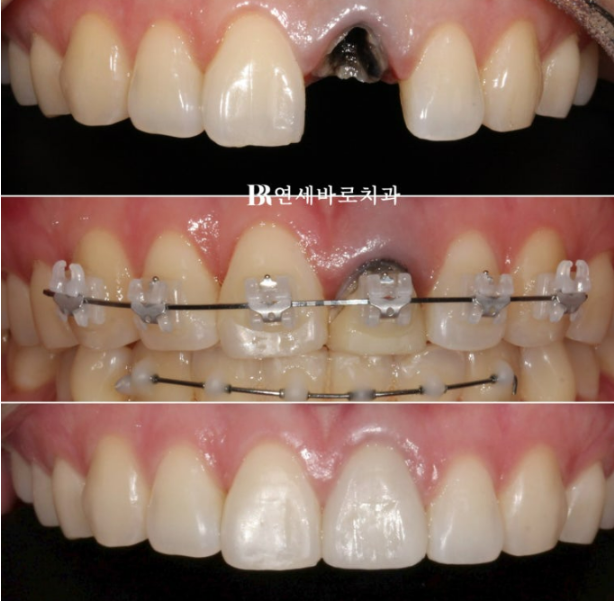

앞니가 부러져서 임플란트와 뼈이식을 해야한다 라는 내용을 듣고 오신 분입니다.

당장 빼고 임플란트 하기 전 혹시나 교정으로 살려 쓰는 방법도 있지 않을까 하여 찾아오신 분입니다.

치아가 부러진 위치가 뿌리여서 지금상태로는 크라운으로 회복이 불가능하니 발치하는 방법 밖에 없습니다.

하지만 교정으로 치아를 뼈속부터 끌어내려 정출시키면 크라운 해서 살려 쓸 수 있습니다.

부러진 치아가 까맣게 변색이 되어서 잇몸이 어둡게 비쳐 보이는 부분도 교정으로 어느정도는 가릴 수 있습니다.

윗니에는 치아 뿌리까지 움직이기 수월하도록 클리피씨 장치를, 배열이 삐뚠 아랫니에는 부분교정용 MTA 장치를 붙여서 교정을 시작했습니다.

부러진 치아에 임시치아를 씌운 상태로 클리피씨를 붙이고 교정을 진행합니다.

최종 크라운까지 예쁘게 들어갔습니다.